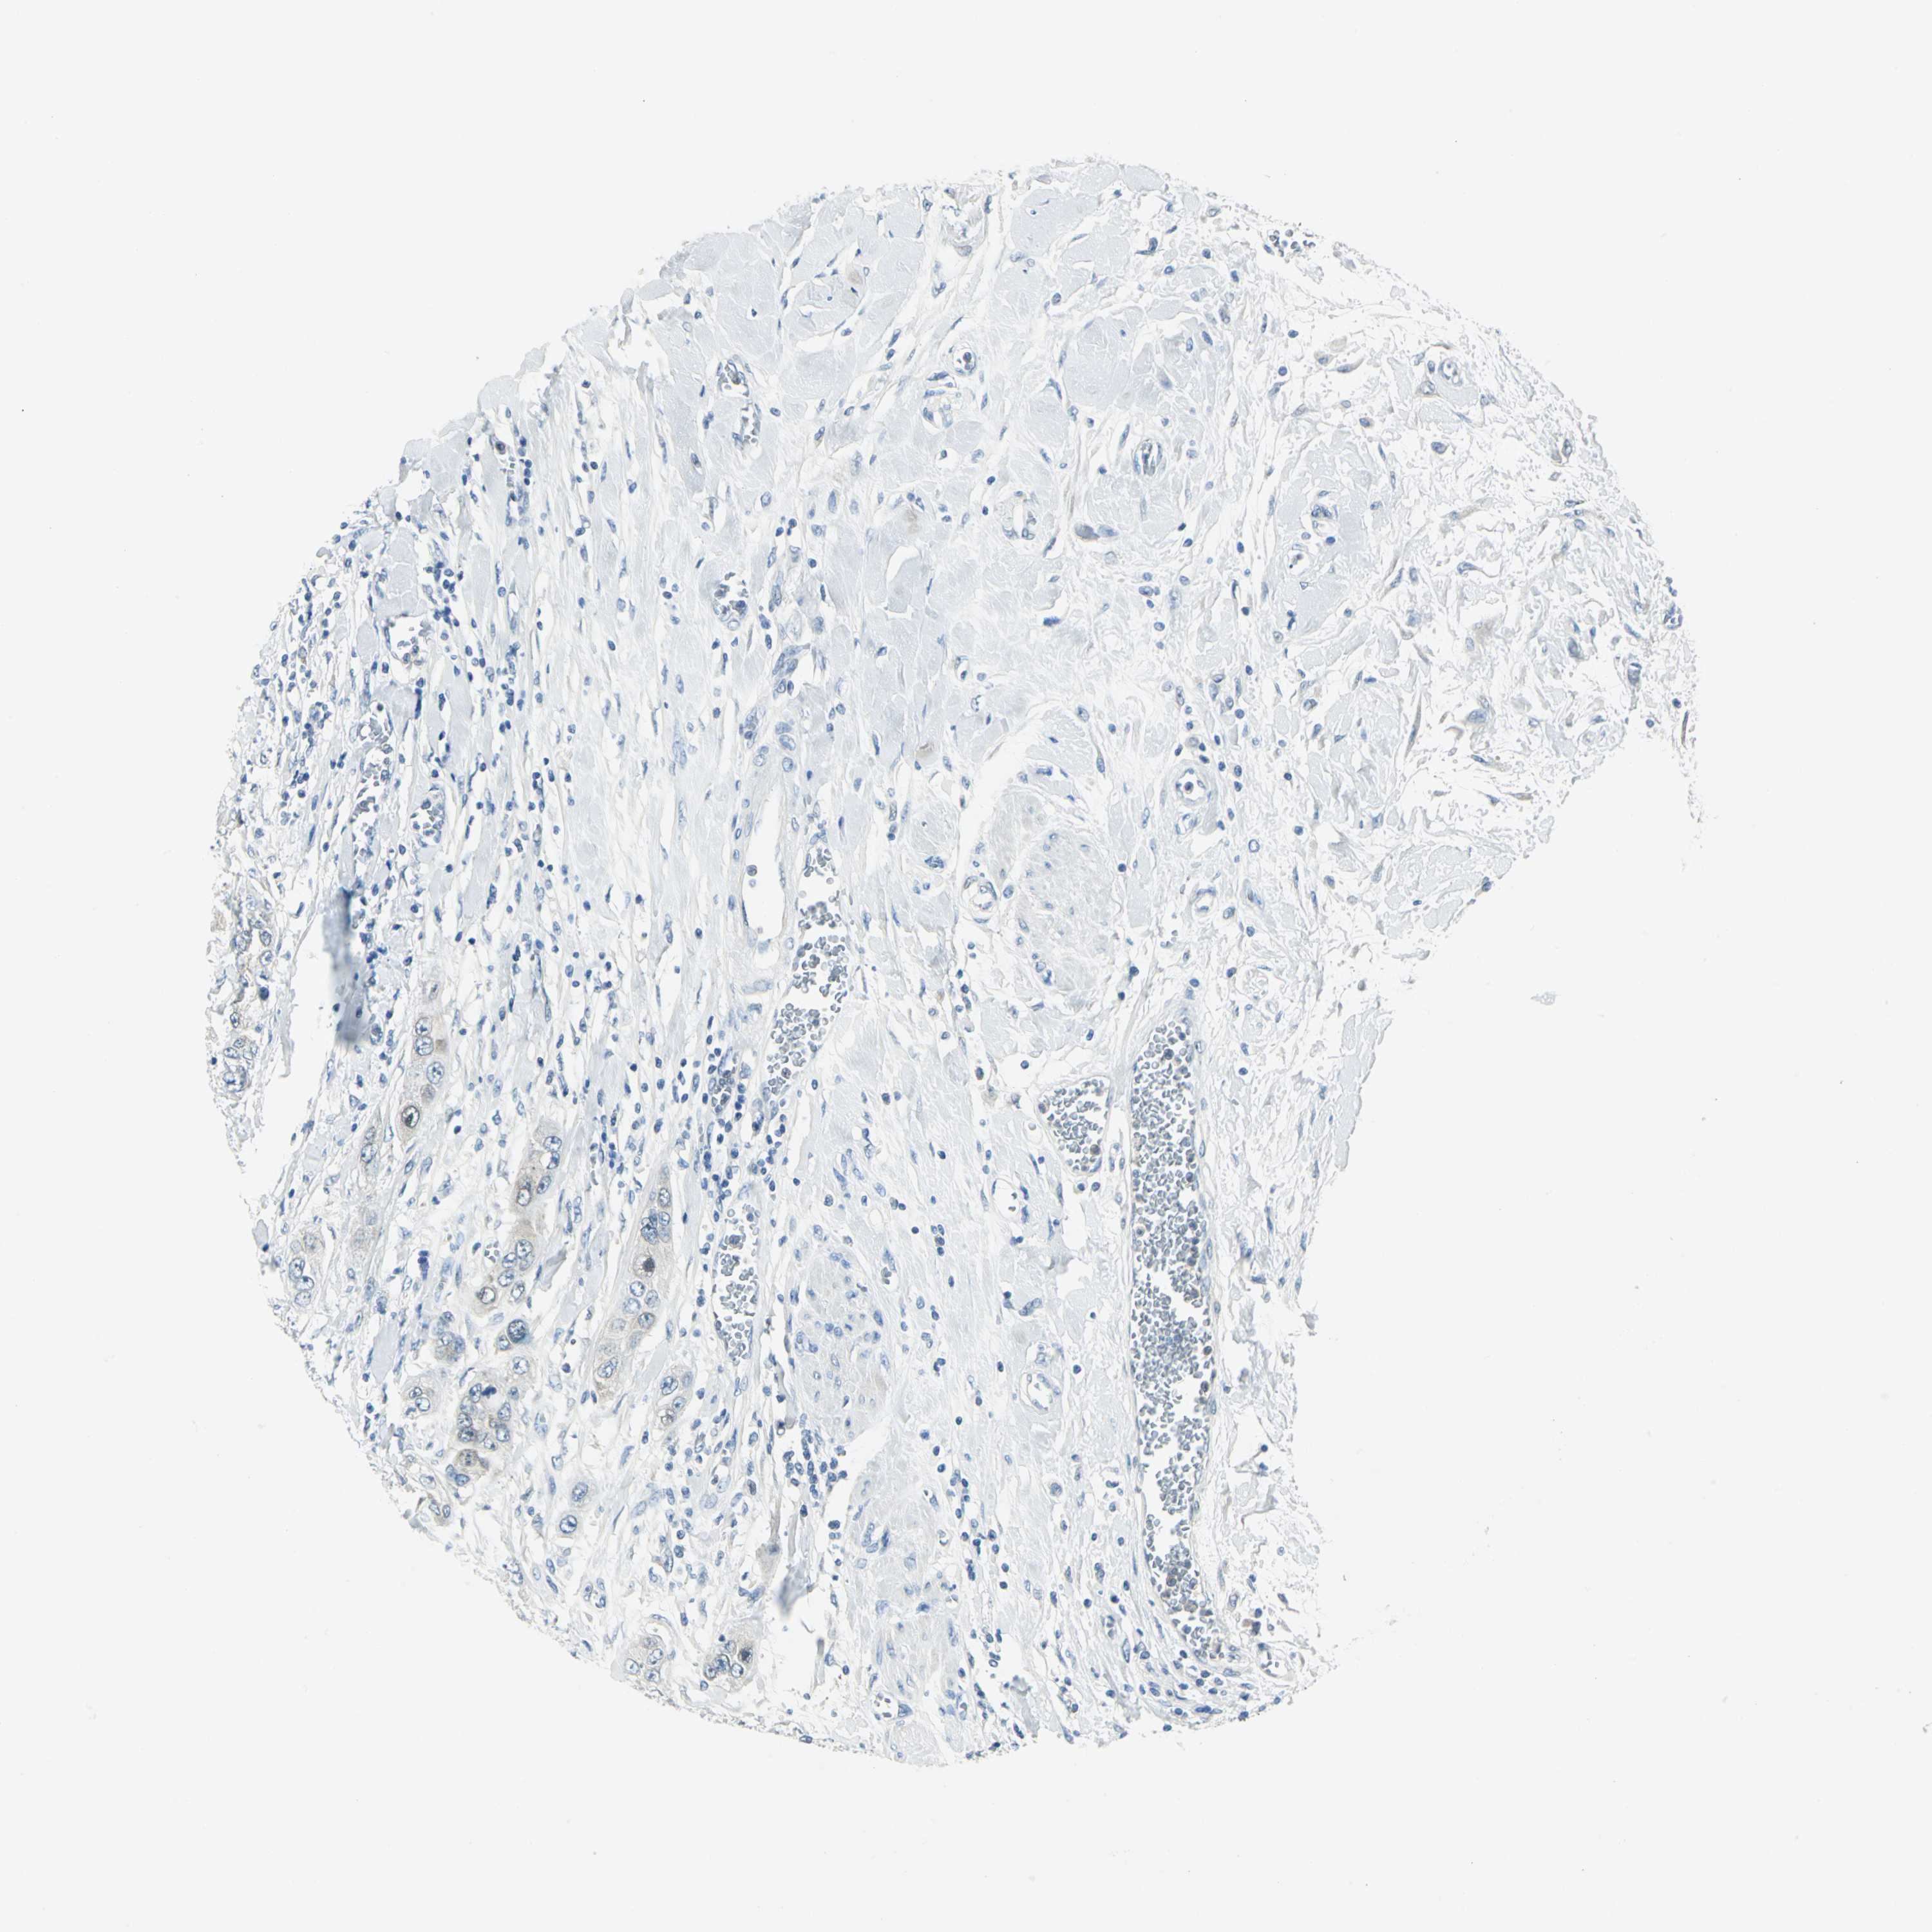

PANCREATIC CANCER - Protein expressioni

A mouse-over function shows sample information and annotation data. Click on an image to view it in a full screen mode. Samples can be filtered based on level of antibody staining by selecting one or several of the following categories: high, medium, low and not detected. The assay and annotation is described here.

Note that samples used for immunohistochemistry by the Human Protein Atlas do not correspond to samples in the TCGA dataset.

Antibody stainingi

Antibody staining in the annotated cell types in the current human tissue is reported as not detected, low, medium, or high, based on conventional immunohistochemistry profiling in selected tissues. This score is based on the combination of the staining intensity and fraction of stained cells.

Each image is clickable and will lead to virtual microscopy that enables deeper exploration of all samples and also displays staining intensity scores, fraction scores and subcellular localization as well as patient and tissue information for each sample.

Antibody HPA004177

Antibody CAB006252

Staining

High

Medium

Low

Not detected

Intensity

Strong

Moderate

Weak

Negative

Quantity

>75%

75%-25%

<25%

None

Location

Nuclear

Cytoplasmic/membranous

Cytoplasmic/membranous,nuclear

Adenocarcinoma, NOS

Adenocarcinoma, metastatic, NOS